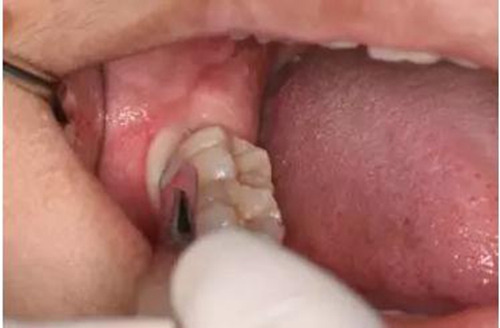

圖6. 從37頰側(cè)中份齦溝內(nèi)開始切開,向磨牙后區(qū)延伸

圖7.切開47遠(yuǎn)中齦溝并延長至磨牙后區(qū)約1cm。

圖8.形成一個(gè)只有水平切口的小袋形口